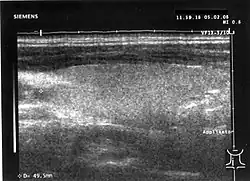

Eine vermutete oder vorhandene Vergrößerung der Schilddrüse kann mit Hilfe einer Schilddrüsensonographie bestätigt werden. Dabei zeigt sich ein im „gesunden“ Schilddrüsengewebe nicht vorkommendes inhomogenes Muster, bei dem sich echoarme und echoreiche Regionen abwechseln. Bei den echoarmen Regionen handelt es sich um die Entzündungsherde der Erkrankung. Sie stellen sich am Monitor dunkel dar, da sie den Schall schlechter reflektieren als normales Schilddrüsengewebe (siehe Untersuchung der Schilddrüse). Das Ausmaß der Schilddrüsengefäßversorgung, der Vaskularisation, lässt sich ebenfalls darstellen. Sie ist bei der subakuten Thyreoiditis de Quervain verringert bis normal.[16] Dies unterscheidet die Thyreoiditis de Quervain beispielsweise vom Morbus Basedow, bei dem die Vaskularisation wesentlich ausgeprägter ist.[16]

Subakute Thyreoiditis im Ultraschall: diffuse Echoarmut.

Subakute Thyreoiditis im Ultraschall: diffuse Echoarmut. -

Zum Vergleich: normale Echogenität der Schilddrüse

Zum Vergleich: normale Echogenität der Schilddrüse -